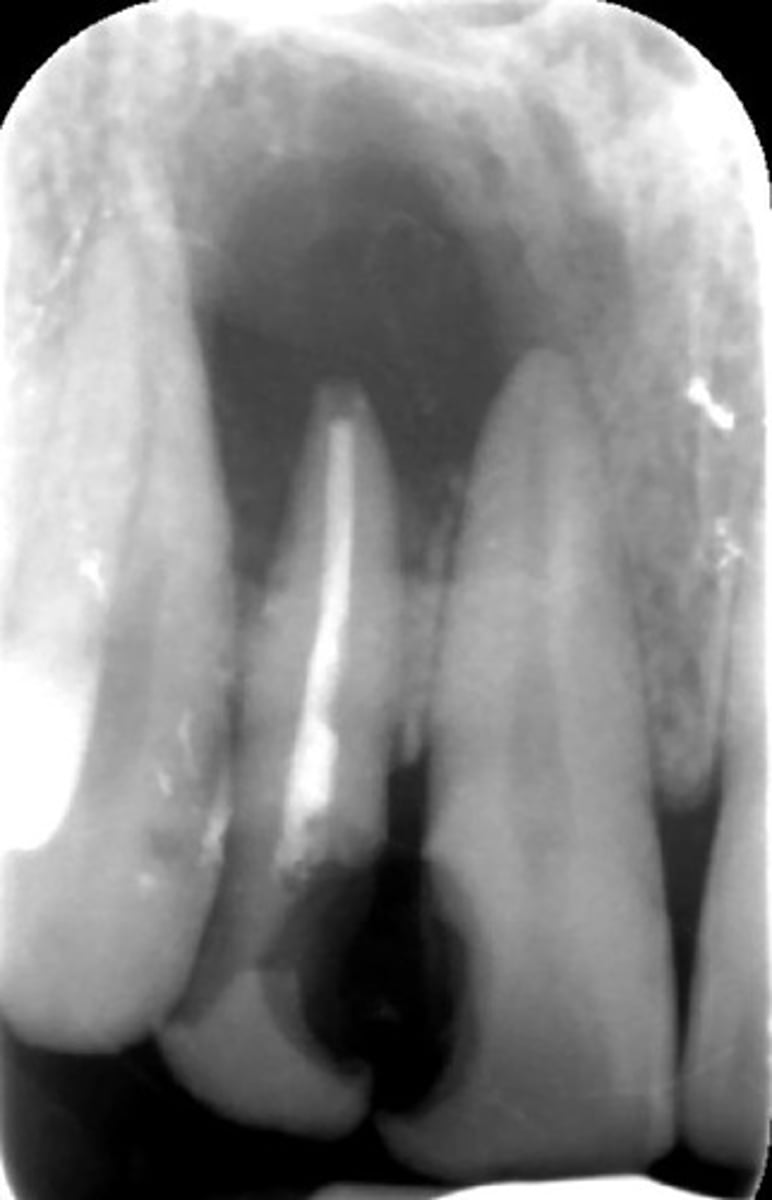

How would you describe the following lesion?

Multiple mixed density periapical target-like entities

The teeth are vital. What category would you put this lesion into?

dysplasia (PCOD)

what could be a differential diagnosis for this lesion?

A. radicular cyst

B. periapical granuloma

C. PCOD (stages 2/3)

D. apical rarefying osteitis